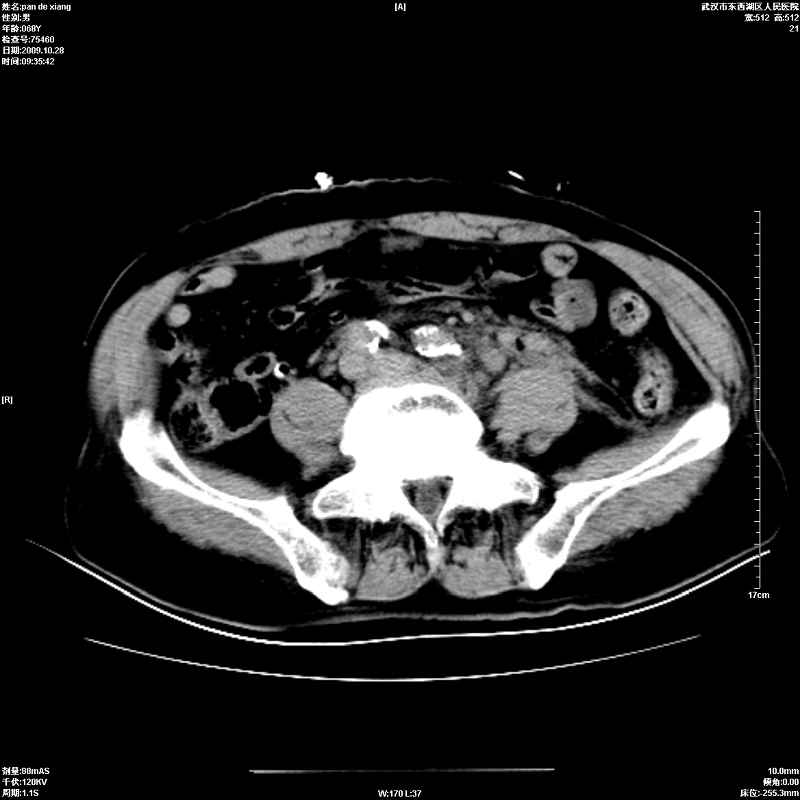

以下是引用杀毒软件在2009-10-28 20:41:00的发言:[br]结合临床考虑---白血病双肾改变或淋巴瘤。

以下是引用zxl51642在2009-10-29 9:59:00的发言:[br]结合临床“单克隆免疫球蛋白血症”,考虑双肾为继发损害并肾功能不全(尿中大量igg及少量iga、igm等大分子免疫球蛋白滤出所致继发损害),椎前软组织肿块为髓外造血。与浆细胞瘤有区别,平扫时有战友说的很清楚。